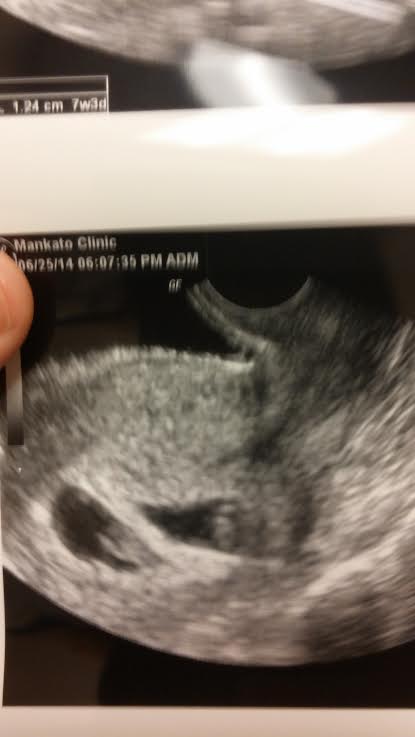

Well had my first ultrasound today, everything looked good the heartbeats are right on. Yep I said heartbeats, it's twins!!!!! I was so surprised, we don't have twins in the family but I guess you have to start with someone. DH is so excited, but I don't think it has sunk in yet and I am more worried than excited. The doc kept my due date the same (Feb 1st), but said I would probably go early.

6/25/14 3rd Ultrasound...Heartbeats!! Baby A 150bpm Baby B 158bpm <3 Beta #5 232,134!!!